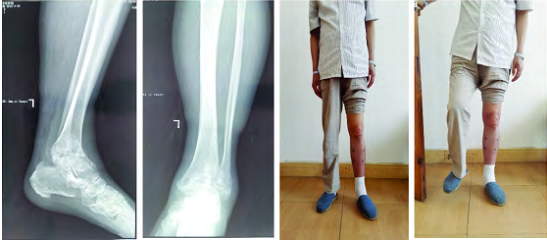

踝关节开放性损伤伴感染 3 年,感染控制后 6 个月行踝关节融合术

Ilizarov 外固定架主要应用于合并复杂畸形或软组织条件不良的严重足踝病变,在融合的同时,可以矫正畸形,在临床上应用较广。